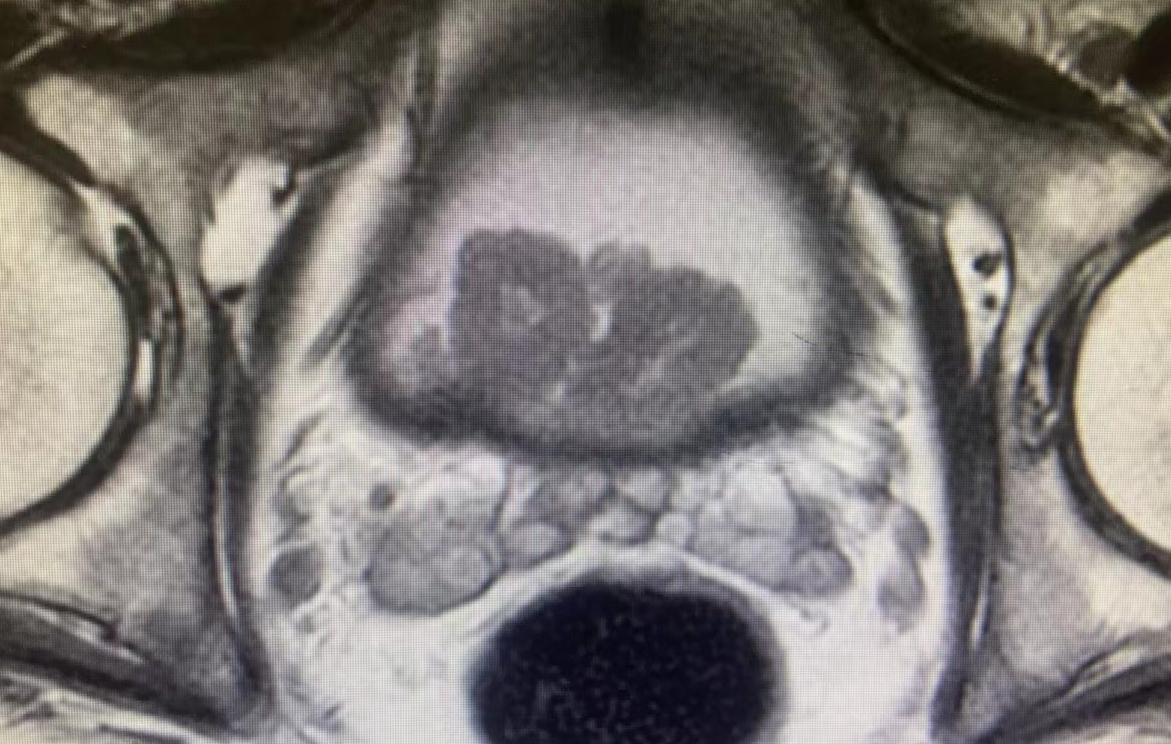

入院后,詹辉教授团队对李先生进行了详细的病史询问和术前评估检查。盆腔磁共振检查发现,膀胱呈现多发肿瘤,最大瘤体4.0x2.7x2.2cm,肿瘤组织向下侵犯前列腺部。取活检后病理结果提示:膀胱高级别尿路上皮癌,术前诊断为:膀胱高级别尿路上皮癌(T3NxMx)。同时入院检查发现患者心脏功能极差,超声心动图提示:左心室壁弥漫性运动减弱,心脏射血分数27%,不到正常人心脏射血功能的一半;动态心电图提示:频发室性过早搏动,心脏自主神经功能调节失调;冠脉CT提示:左前降支中重度狭窄,N端脑钠肽前体:1990pg/ml。此外由于肿瘤侵犯前列腺,长期梗阻导致患者肾功能不全、尿路耐药摩根氏菌感染,同时还合并有高血压2级、2型糖尿病、中度肺通气功能障碍、支气管扩张症等疾病。